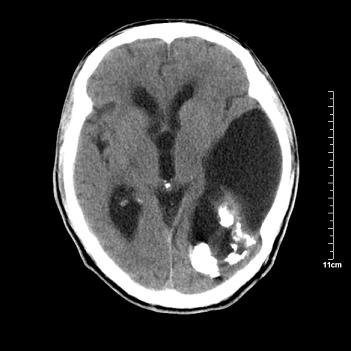

男性患者,72岁,近两天头晕来我院就诊。 因患者血压太高而未做增强,建议病人去市医院做mri检查。等得到mri随访结果再公布给大家。 测及左颞顶枕叶病灶ct值分别为5hu 30hu 729hu。

考虑左侧颞顶枕叶少突胶质细胞瘤。 今天随访患者手术病理结果 病理回报为胶质瘤2级 钙化

左侧颞顶枕叶大片状低密度影,呈均一水样密度,边界清楚,病灶边缘不规则片状钙化,左侧脑室后角扩大,中线结构未见移位,综合来看不像肿瘤,软化灶,钙化不好解释

左侧颞顶枕叶巨大囊性病灶,灶内见小片实性区且灶内及灶周围大量团块状钙化影,灶周水肿少.左侧室枕角内见环形钙化,可见较清晰前壁,钙化与室壁似有间隙.

考虑1寄生虫病2表皮样囊肿钙化3血管畸形,其他不排

今天追踪患者家属手术病理结果 病理回报为胶质瘤2级并钙化

病理回报为胶质瘤2级并钙化